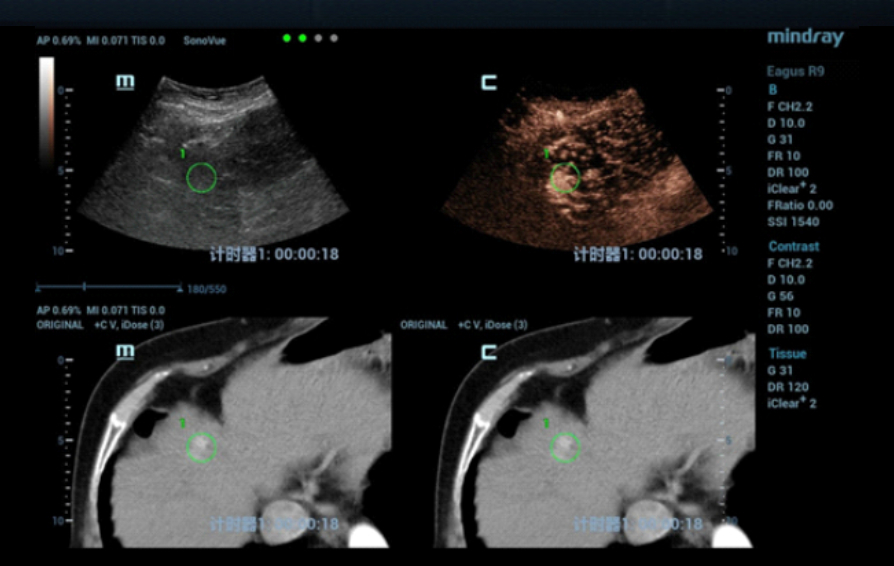

W konwencjonalnym obrazowaniu USG w skali szaro?ci nie uda?o si? uwidoczni? guza w segmencie IV zaobserwowanego w badaniu TK jamy brzusznej. W badaniu USG z kontrastem (contrast-enhanced ultrasound, CEUS) zmiana wykazywa?a wzmo?one unaczynienie w fazie t?tniczej (Obraz 2.) z izointensywnym wzmocnieniem w fazach wrotnej i pó?nej (Obraz 3.)./p>

U pacjentki zaplanowano zabieg ablacji mikrofalowej (microwave ablation, MWA) pod kontrol? USG, jednak z uwagi na fakt, ?e nie uda?o si? uwidoczni? zmiany w konwencjonalnym badaniu USG, w celu zapewnienia dok?adnego pozycjonowania elektrody mikrofalowej wykorzystano obrazowanie metod? fuzji obraz√≥w: ultrasonograficznego i TK z kontrastem (Nagranie 1, Obraz 4вАУ7).

Guz by? izoechogeniczny i nie mo?na by?o wyra?nie uwidoczni? go w badaniu USG 2D w skali szaro?ci, zatem konwencjonalna kontrola wy??cznie z zastosowaniem USG mog?a skutkowa? niedok?adnym pozycjonowaniem i niepe?n? ablacj?. Z kolei obrazowanie z wykorzystaniem fuzji obrazów uzyskanych w badaniu USG w czasie rzeczywistym z danymi uzyskanymi w badaniu TK z kontrastem umo?liwi?o dok?adne pozycjonowanie elektrody i skuteczne leczenie zmiany metod? przezskórnej MWA. Przed zabiegiem przeprowadzono badania CEUS w celu potwierdzenia umiejscowienia guza oraz po zabiegu w celu oceny obszaru poddanego ablacji i potwierdzenia skuteczno?ci leczenia.